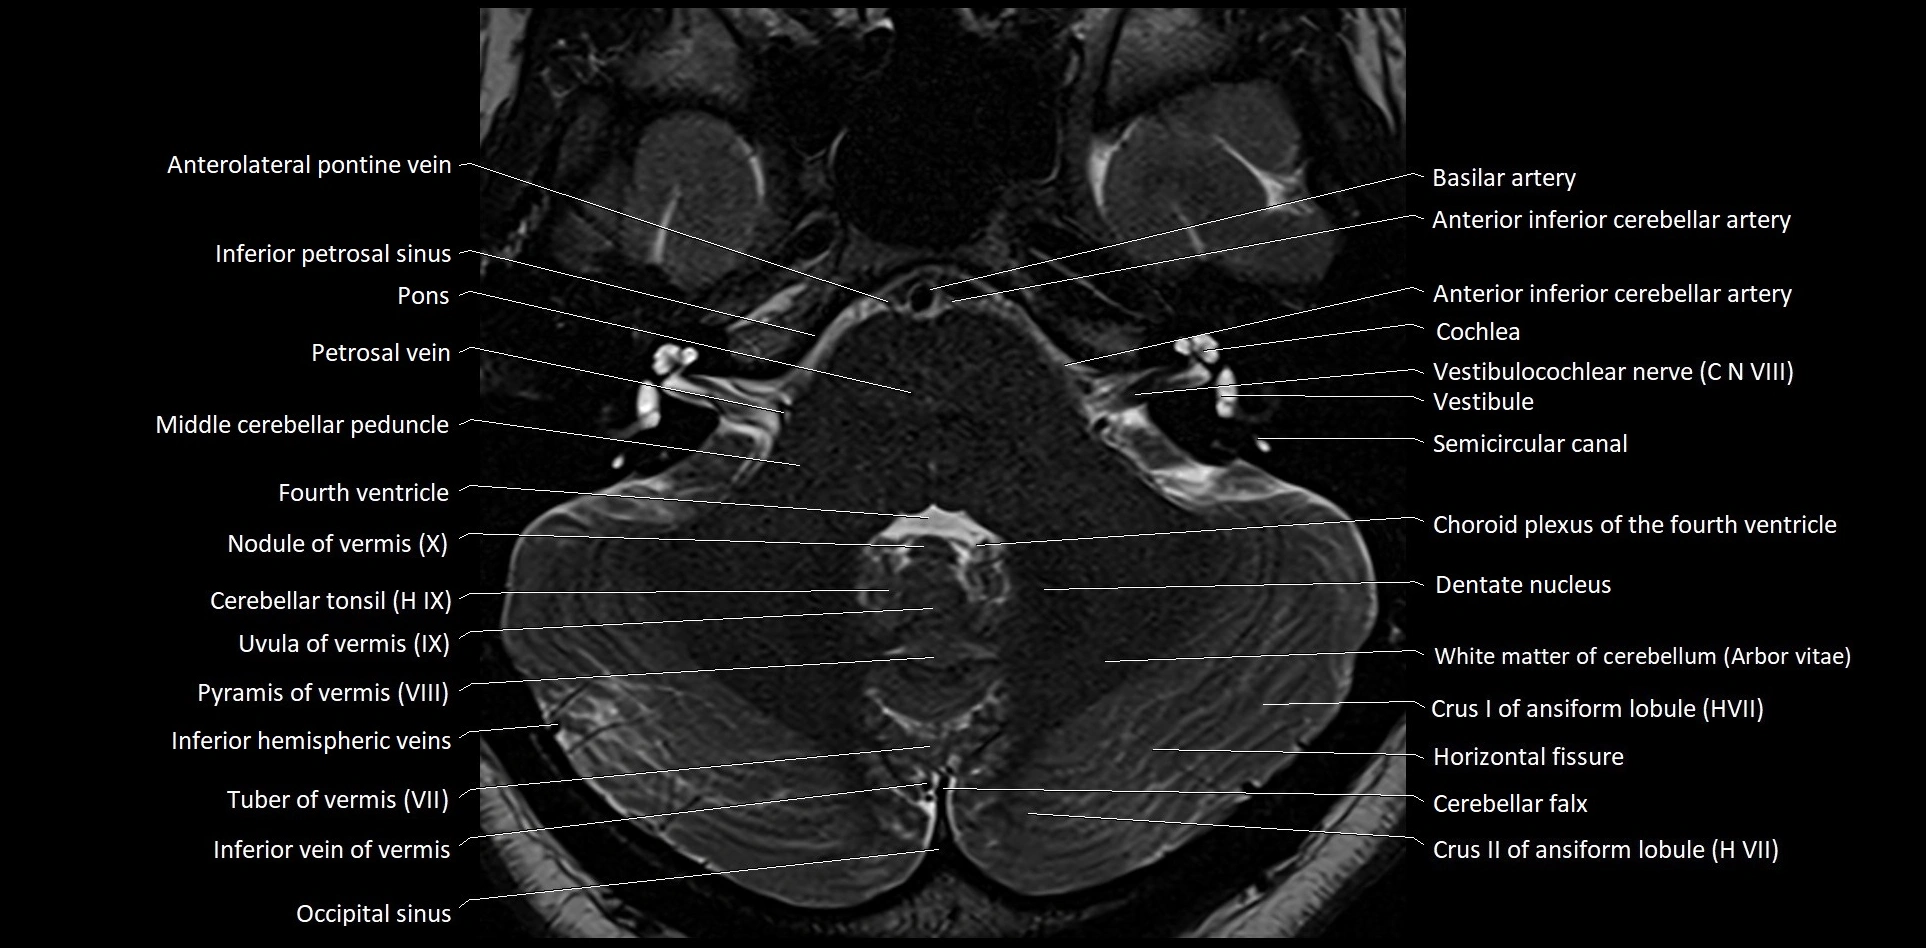

- Anterolateral pontine vein

- Cerebellar tonsil (H IX)

- Choroid plexus

- Cochlea

- Crus I of ansiform lobule of cerebellum

- Crus II of ansiform lobule of cerebellum

- Dentate nucleus

- Inferior cerebellar veins

- Inferior hemispheric veins of the cerebellum

- Inferior petrosal sinus

- Inferior vein of vermis

- Middle cerebellar peduncle

- Nodule of vermis

- Nodule of vermis (X)

- Occipital sinus

- Pyramid of vermis (VIII)

- Pyramis of vermis

- Semicircular Canals

- Transverse sinus

- Tuber of vermis (VII)

- Uvula of vermis

- Uvula of vermis (IX)

- Vestibulocochlear nerve (Cranial nerve VIII)

- White matter of cerebellum (Arbor vitae)